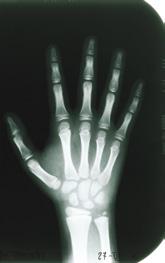

These beams are very interesting And they have amazing powers. They can travel through a brick wall Through a hand or through a flower.

Look at the pictures of the locomotor system. Add the missing arrows.

Wrist Skull

Elbow

Humerus

Shoulder

Ribs

Femur

Knee

Tibia

Ankle